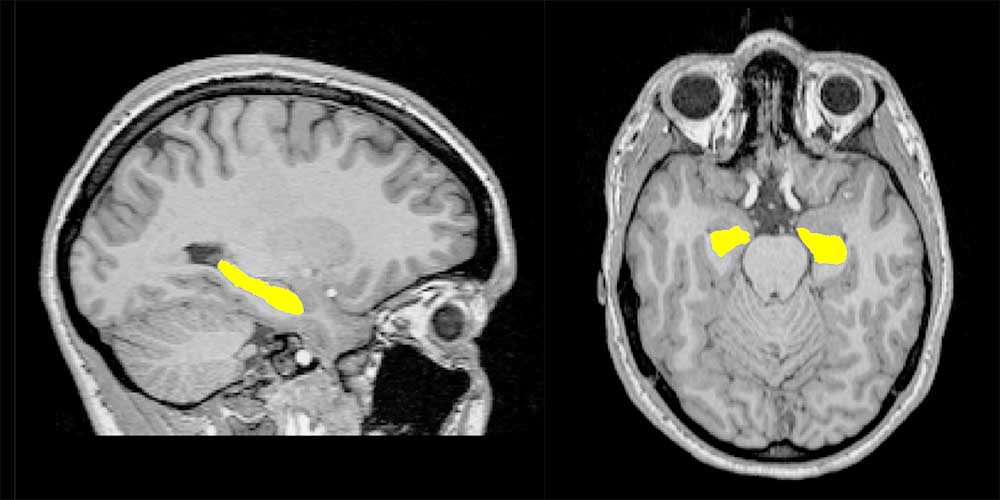

Schizophrene Psychosen sind eine häufig vorkommende Gruppe psychiatrischer Erkrankungen, an deren Entstehung biologische, soziale und Umweltfaktoren beteiligt sind. Die Erkrankung geht mit Veränderungen der Hirnstruktur einher. So ist beispielsweise bei Betroffenen der Hippocampus im Schläfenlappen häufig kleiner als bei gesunden Menschen. Ob diese Veränderungen der Hirnstruktur eine Folge der Krankheit und der damit einhergehenden Medikation darstellen oder bereits vor ihrem Ausbruch zu beobachten sind, ist bisher nicht geklärt.

Eine Forschungsgruppe der Universität Basel um Fabienne Harrisberger und Stefan Borgwardt haben in einer aktuellen Studie die Hirnstruktur von Personen untersucht, bei denen sich eine Psychose zum ersten Mal manifestierte, oder die ein erhöhtes Psychoserisiko aufweisen. Die Wissenschaftler der Erwachsenen-Psychiatrischen Klinik der Universitären Psychiatrischen Kliniken (UPK) und der Transfakultären Forschungsplattform Molekulare und Kognitive Neurowissenschaften (MCN) konnten zunächst beobachten, dass es keine nennenswerten Unterschiede des Hippocampus zwischen Hochrisikopersonen und Patienten gab.

In einem zweiten Schritt haben sie zusammen mit Wissenschaftlern der Transfakultären Forschungsplattform untersucht, ob bekannte, mit Schizophrenie assoziierte Risikogene in Zusammenhang mit dem Hippocampus stehen. Dies scheint der Fall zu sein: Je höher die Anzahl der Risikogene einer Person war, desto kleiner war das Volumen des Hippocampus dieser Person, und zwar unabhängig davon, ob es sich um Hochrisikoprobanden oder Patienten handelte. Dies bedeutet, dass eine Gruppe von Risikogenen in Zusammenhang mit der Volumenminderung einer kritischen Hirnregion steht, bevor sich die Erkrankung manifestiert.